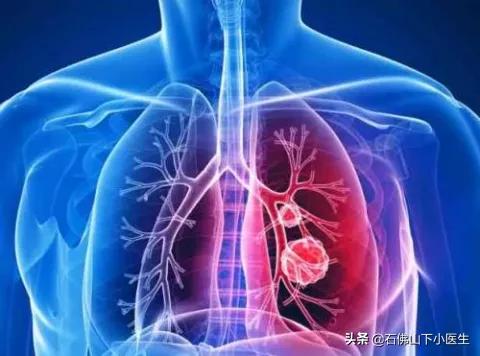

I. Tomodensitométrie hélicoïdale à faible dose du thorax

• Ce scanner spiralé à faible dose est principalement utilisé pour le dépistage du cancer du poumon. Le cancer du poumon est le cancer dont l'incidence et le taux de mortalité sont les plus élevés dans notre pays, et l'examen physique ne peut certainement pas passer à côté des poumons.

• La tomodensitométrie spiralée à faible dose est préférée pour le dépistage du cancer du poumon en raison de la faible dose de radiation par rapport à la tomodensitométrie conventionnelle.

• De nos jours, le nombre de personnes qui découvrent de petits nodules dans leurs poumons est en augmentation, ce qui peut s'expliquer par l'augmentation du nombre de personnes qui se soumettent à des examens médicaux. Par rapport aux personnes qui ne passent pas d'examens médicaux, les examens médicaux permettent de détecter les nodules pulmonaires à temps, puis de les examiner régulièrement. Si le médecin soupçonne que les nodules pulmonaires peuvent être malins, une intervention chirurgicale peut être pratiquée en temps utile.